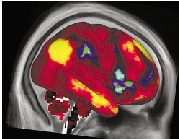

3D大脑图像